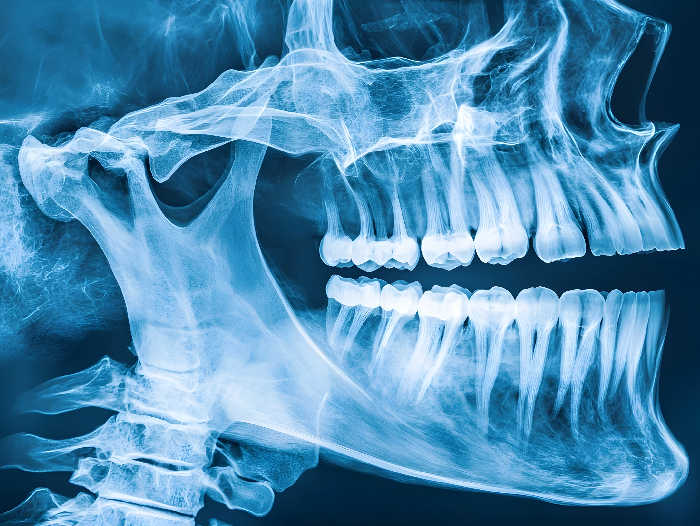

El equipo investigador del proyecto europeo HYDROHEAL desarrollará micropartículas encapsuladas en hidrogeles biorreabsorbibles y autoendurecibles, que permitirán incorporar y transportar diversos principios activos farmacológicos. Estos biomateriales actuarán como soporte temporal para la regeneración ósea y, al mismo tiempo, permitirán la liberación controlada y dirigida de los principios activos, mejorando la eficacia del tratamiento y reduciendo significativamente el riesgo de infección y de rechazo de los implantes. De este modo, el proyecto se centra en desarrollar nuevos biomateriales para el tratamiento de fracturas vertebrales y alveolares (en la mandíbula, en la base de los dientes), especialmente en casos complejos derivados de la osteoporosis, cáncer o traumatismos.